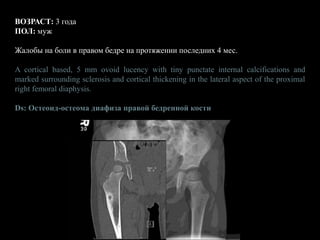

ВОЗРАСТ: 3 года

ПОЛ: муж

Жалобы на боли в правом бедре на протяжении последних 4 мес.

A cortical based, 5 mm ovoid lucency with tiny punctate internal calcifications and

marked surrounding sclerosis and cortical thickening in the lateral aspect of the proximal

right femoral diaphysis.

Ds: Остеоид-остеома диафиза правой бедренной кости